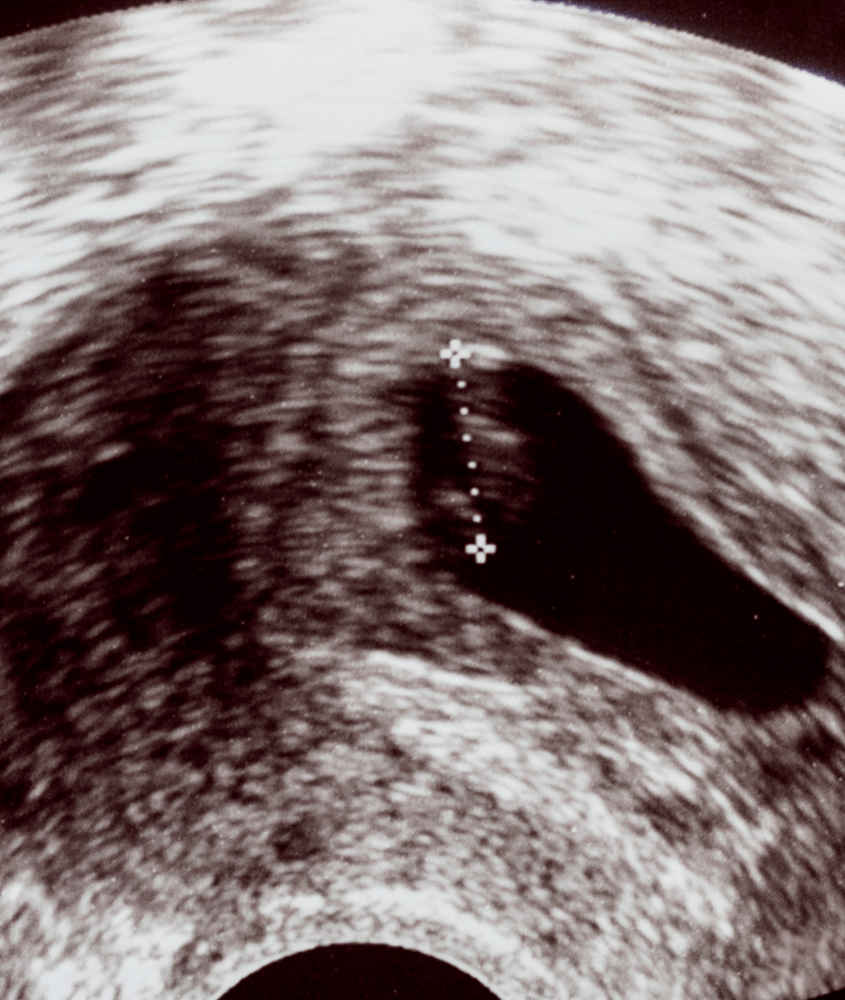

Dr. Alan B. Copperman, Co-Medical Director of Reproductive Medicine Associates of New York, discusses Asherman’s Syndrome- causes, treatments and the use of 3D ultrasound.